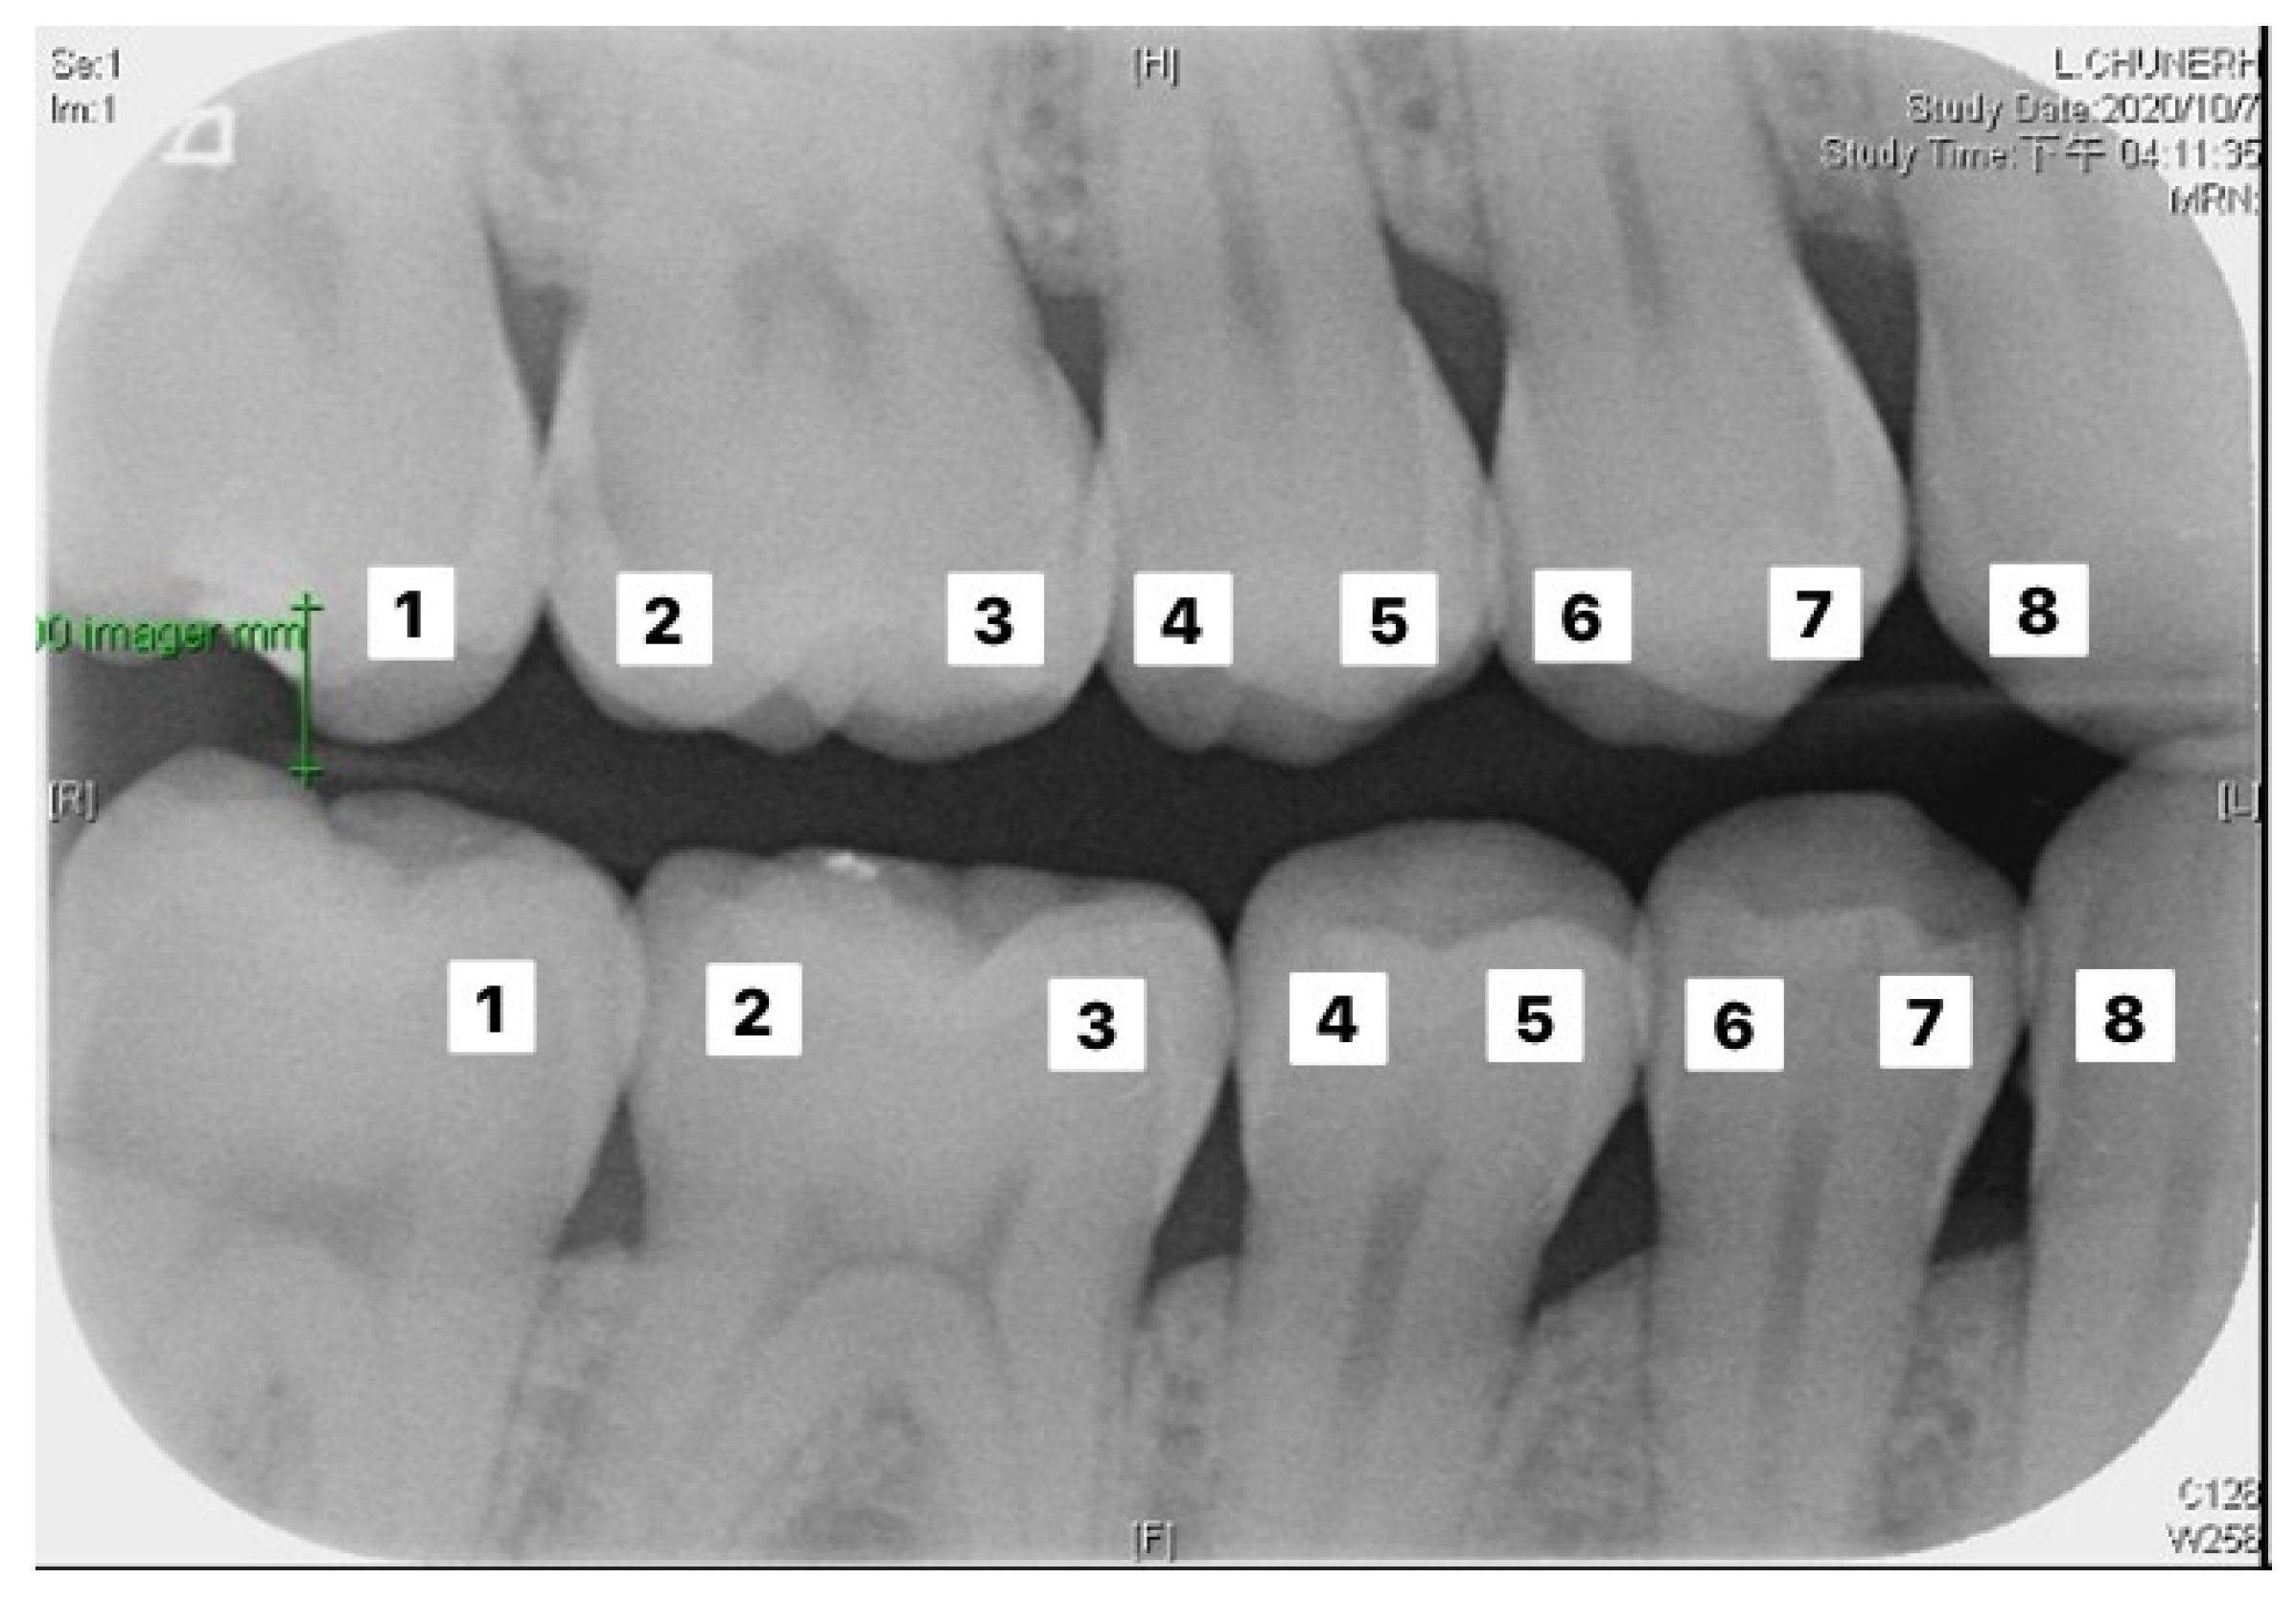

The validation set was used to evaluate the performance of the two established models. The actual number of findings in the photo with the predicted number of findings in the photo were compared to calculate the accuracy. The formula of accuracy is shown in Equation (7). Table 4 and Table 5 correspond to the execution results of the upper and lower teeth in Figure 9, respectively.

Figure 9.

Image example of outer teeth for validation (from left to right, in order of 1–8).